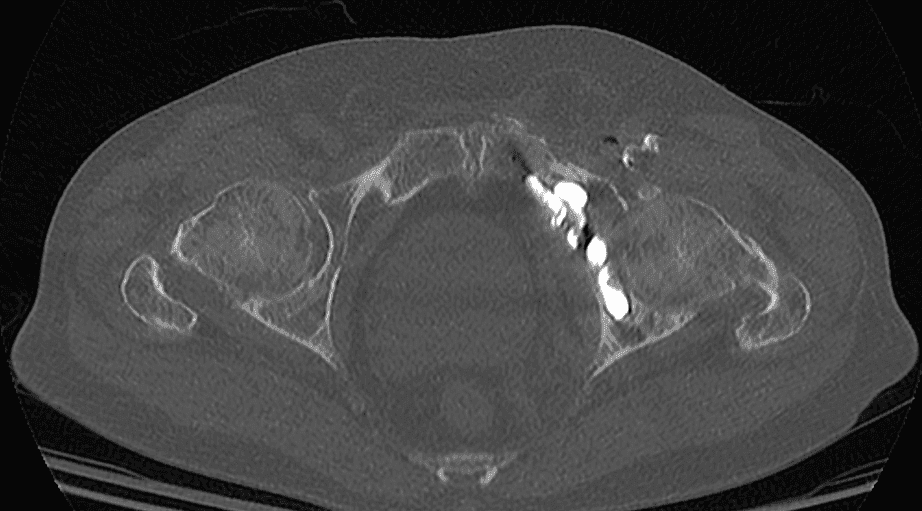

Contrôle post-procédural :

Un contrôle scanner final permet de vérifier la position du vissage et la qualité de la réduction anatomique, garantissant ainsi le succès de l’intervention.